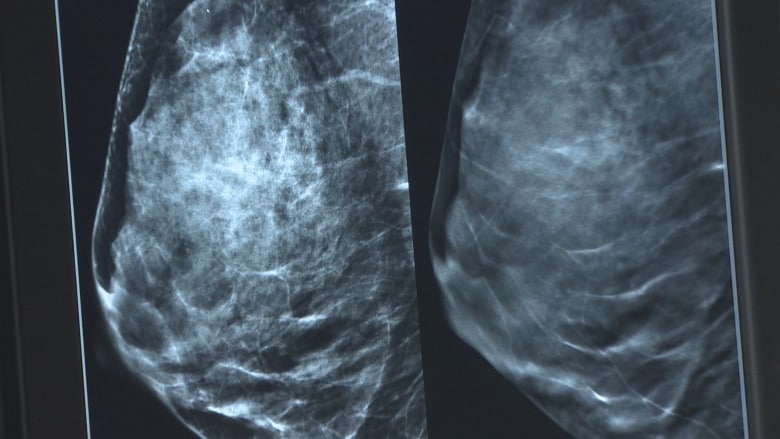

多久检查一次?

Ryan Woods 补充说,非移民妇女的检查率 51.2%,仍然远远低于BC癌症协会的目标 – 70%。

BC 省癌症协会表示,八分之一的女性会在一生中的某个阶段患上乳腺癌,因此应该定期进行检查。

该机构称,BC省为 40 至 74 岁的女性提供免费的乳房 X 光检查,并不需要医生的处方。

对于母亲或姐妹患有乳腺癌的妇女来说,她们患乳腺癌的可能性是其他人的的两倍之多,因此每年都要进行乳房 X 光检查。

对于那些年龄 在50 到 74 岁之间,没有乳腺癌家族史的人,BC 省癌症协会建议每两年进行一次乳房 X 光检查。

75岁及以上的女性,应该每两到三年进行一次检查。